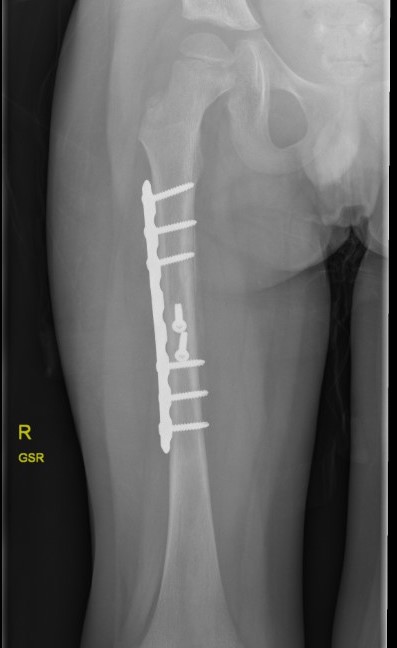

Femur plates

Indication

- length unstable fractures (spiral / comminuted)

- distal or proximal fractures

Options

Open plating

Submuscular bridge plating

Technique

- supine on radiolucent table or traction table

- proximal and distal incisions

- blunt dissection to periosteal layer

- run bristow or cobb elevator submuscularly

- 3.5 or 4.5mm LCP plate submuscularly

- indirect reduction techniques

- if inadequate reduction need to open